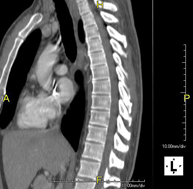

- Columna

Prueba radiológica que consiste en obtener imágenes de las vértebras dorsales de alta definición anatómica mediante el empleo de un equipo de TC (Tomografía Computarizada). Indicaciones: dolor dorsal, estudio de desviaciones de la columna, traumatismo. - TC Columna lumbar

Prueba radiológica que consiste en obtener imágenes de las vértebras lumbares de alta definición anatómica mediante el empleo de un equipo de TC (Tomografía Computarizada). Indicaciones: dolor lumbar sin/con irradiación a piernas, dificultad para caminar, traumatismo. - TC Sacro-cóccix